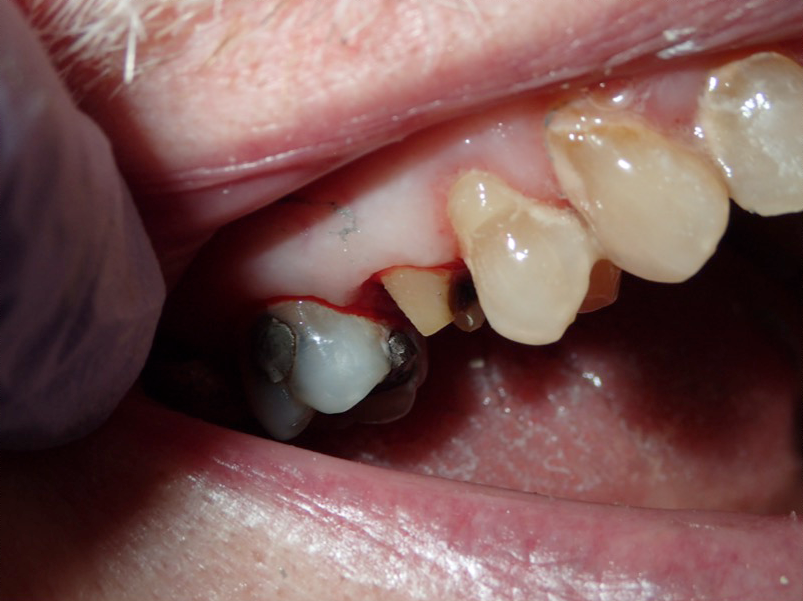

Fig 2. Prepared tooth and margin.

Figure 2

An advantage of using cord technique is that it generally provides an accurate and precise measurement,7,8 physically separating the gingiva away from the prepared margin to allow the clinician to insert light-body material to flow below the margin. Additionally, if a double-cord technique is used, the clinician can leave the bottom cord in place. Moreover, no new equipment is required, and chemicals may not be needed. The clinician needs only the cord and a cord packing instrument. Drawbacks to using cord are the risk of epithelial attachment injury, some pain that may necessitate the use of local anesthesia, a level of technique sensitivity that typically requires practice on the part of the clinician to become skilled, the likelihood of bleeding, and the risk of irreversible gingival injury that may lead to permanent recession.9,10 Figure 2 through Figure 5 show close-up photographs of a prepared tooth and margin, cord being packed, cord in place, and margin after cord removal, respectively.

Figure 6 through Figure 9 demonstrate the use of retraction paste and a cap. An upper bicuspid was prepared (Figure 6), and some bleeding occurred due to the clinician working below the existing restorations. Retraction paste was then applied (Figure 7), but there was still some residual bleeding. The clinician then had the patient close on the retraction cap to stop the bleeding (Figure 8). Some blanching occurred as the patient bit into the cap. The patient will hold that position depending on how much bleeding occurs. Figure 9 shows the exposed margin ready for impressioning. In this case, the retraction cap was kept in place with the patient biting down on it for 2 to 3 minutes instead of 1 to 2 minutes because there was a fair amount of bleeding initially.